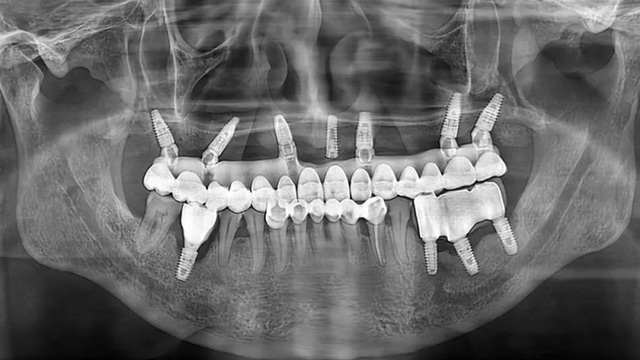

种植手术完成后,沈老师戴上了临时牙,上半口的咀嚼功能得到恢复,嘴巴也不再瘪瘪的了。看着镜子里那一排似曾相识的上牙,他感觉像做梦一样,回想起这几年所受的折磨,他感慨不已。

完成上半口戴牙后